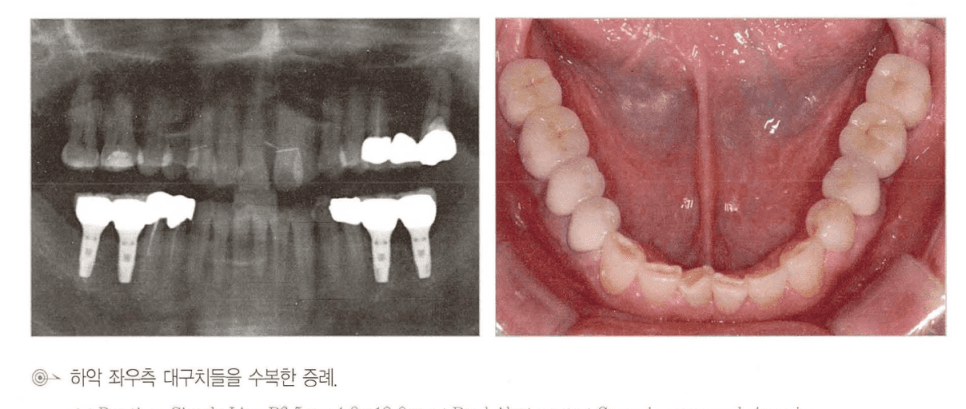

[그림 2] 상악 우측 대구치 구간을 임플란트 2개 + 중간 pontic 형태의 3-unit 브리지로 수복한 실제 임상 증례. 파노라마와 구강 내 사진에서 배치를 확인할 수 있습니다.

구치부 3개 상실이라고 해서 반드시 임플란트 3개를 모두 심어야 하는 것은 아닙니다. 양쪽 끝에 2개를 심고 중간을 pontic으로 연결하는 3-unit 설계가 임상에서 널리 쓰이며, 세 가지 실질적 이점이 있습니다.

- 수술 횟수·비용·회복 기간 감소 — 식립 개수가 줄면서 전신 부담이 작아집니다.

- 보철물 적합도 향상 — 임플란트가 너무 많이 나란히 배치되면 인상 정밀도와 패시브 핏 확보가 어려워집니다.

- 잇몸 건강에 유리 — 임플란트 사이 치간 유두(papilla)보다 임플란트–pontic 경계의 연조직 형태가 상대적으로 더 안정적입니다.

⚠️ 단, 상악 구치부처럼 골질이 약하거나 상악동 골이식이 필요한 증례에서는 교합력 분산을 위해 3개를 모두 심는 편이 안전합니다. “항상 2개 + pontic” 같은 규칙이 아니라 환자별 골질·교합력 평가가 우선입니다.